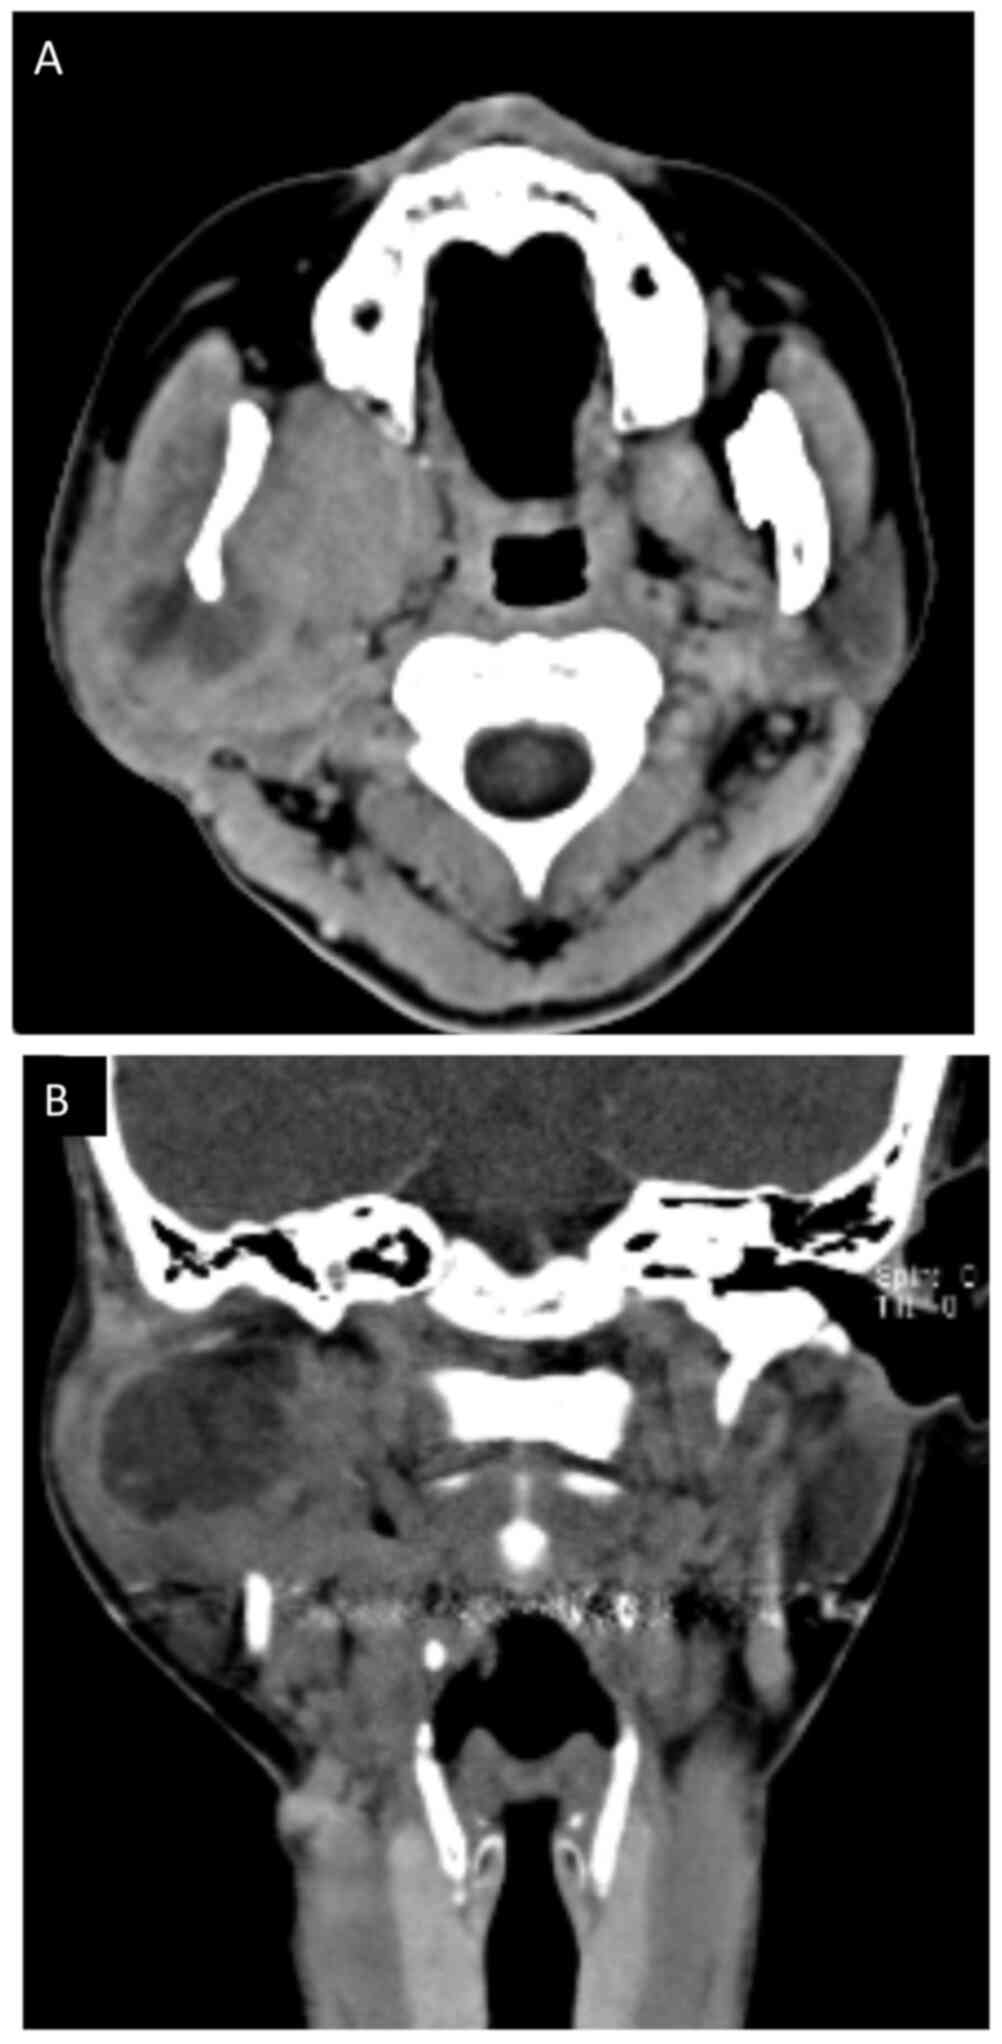

At five months post referral the lower part of the right auricula displayed swelling. Computed tomography (CT) and magnetic resonance imaging (MRI) revealed a space occupying mass (52×50×40 mm) in the infratemporal fossa (Figs. 2 and 3). Fine needle aspiration biopsy (FNAB) was performed at this site and hemoid gelatinous fluid was withdrawn. However, pathological examination of the sample did not lead to final diagnosis. Parotid gland tumor, neurilemoma, primitive neuroectodermal tumor (PNET), conventional HPC, and SFT were cited as differential diagnoses.

Figure 2.

Computed tomography (CT) before treatment. (A) Horizontal and (B) coronal.